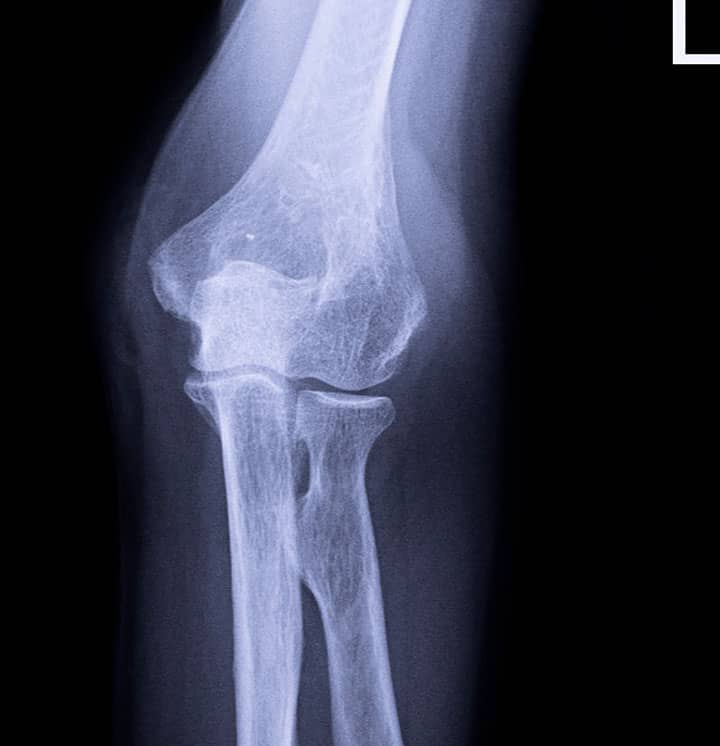

Cotovelo – incidência AP – rotina básica

Justificativa para realização do exame

incidência realizada para o estudo de fraturas, luxações e patologias, como osteomielite, artrite e artrose.

Principais estruturas demonstradas

o rádio e a ulna proximais, o úmero distal e o espaço articular do cotovelo.

Fatores técnicos e posicionamento:

DFF: 1m.

Tamanho do filme/receptor de imagem e sentido: 18x24cm no sentido transversal.

Técnica de referência: 4mAs e 46KV, fora do bucky.

RC: perpendicular ao receptor de imagem, direcionado para a articulação do cotovelo.

Posição do paciente e da parte ou região do corpo: colocar o paciente sentado na extremidade da mesa de exames com o cotovelo totalmente estendido.

Cotovelo – incidência lateral – rotina básica

o rádio e a ulna proximais, o úmero distal e o espaço articular do cotovelo lateralizados.

Técnica de referência: 4mAs e 50KV, fora do bucky.

Posição do paciente e da parte ou região do corpo: colocar o paciente sentado na extremidade da mesa de exames com o cotovelo flexionado a 90°.

Cotovelo com flexão aguda – Método de Jones ou Pierquiu – incidência axial – rotina especial

Incidência realizada para o estudo de fraturas no olécrano e em luxações do cotovelo.

olécrano e imagem superposta do terço distal do úmero e terço proximal de rádio e ulna.